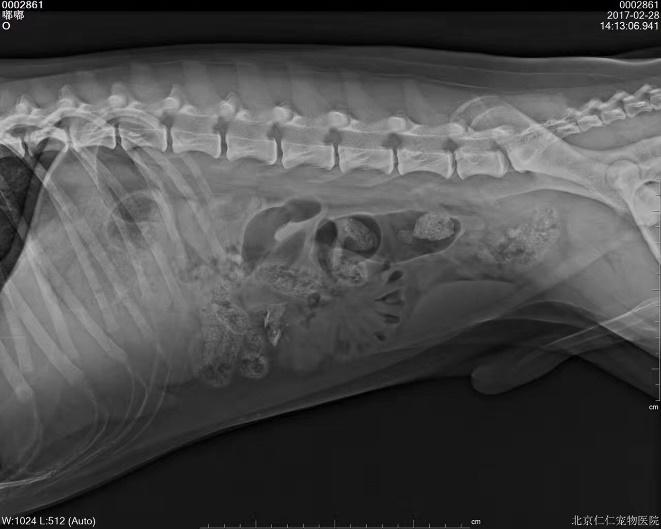

c.X线检查。对于阻线性较强的物质(如金属、骨头)较容易辨别,对于阻线性与策划密度相似的物体较难确定,但是可以通过消化道灌服造影剂判断是否有阻塞或可包裹物体。

机械性肠梗阻的读片要点:1.体积增大;2.形态轮廓变化;3.影像密度变化;4.浆膜细节变化。

金毛 线性异物